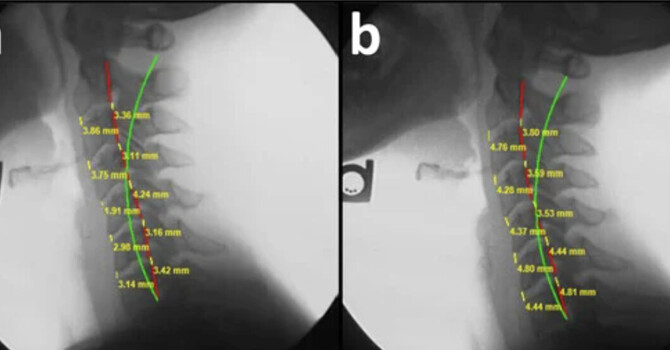

Adult scoliosis is less commonly discussed but widely experienced. Some adults have curves that began in adolescence and were never identified. Others develop scoliosis later in life as discs and joints degenerate unevenly. Before discussing curve size in adults, it helps to distinguish between these two pathways. TAlthough the origin differs, both forms involve progressive mechanical stress when left unaddressed.The same Cobb angle ranges used in adolescents are used in adults. What changes is the driver of progression. Growth is no longer a factor, but cumulative load and degeneration can be just as impactful.The chart below shows how adult scoliosis severity is classified using these same ranges. Many adults are surprised to learn how long their curve may have been present before symptoms appeared. Pain often develops after years of uneven loading, not at the moment the curve forms.Moderate and Severe Curves in Adults. As adult curves move into the moderate and severe ranges, symptoms such as pain, stiffness, and nerve irritation become more common. These symptoms are often related to how forces are distributed through the spine rather than the curve alone.The diagram below illustrates how larger curves increase asymmetric stress on discs and joints.At this stage, treatment focuses on improving balance, reducing abnormal loading, and stabilizing the spine. Medications may reduce discomfort, but they do not change the underlying mechanics driving progression.